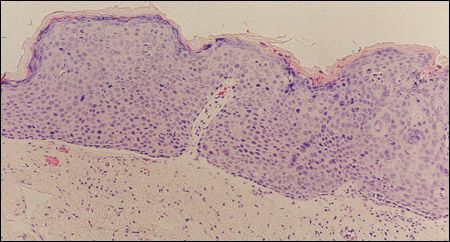

Figure 1 – Biopsy from this case shows architectural failure of maturation throughout the epithelium. Miniscule granular layer produces the thin keratin covering. Subepithelium looks edematous and mildly infiltrated with lymphocytes. (Hematoxylin and eosin stain, original magnification ×100.)

Armed with the diagnosis, which was confirmed on incisional biopsies (Figures 1 and 2), we can wonder whether the "collar" represents a hyperplastic dysplasia; since this area was not sampled, the inference must be considered reasonable but unproven and thus speculative. A markedly papillomatous area on the underside of the glans showed similar pathology on biopsy (Figure 3).